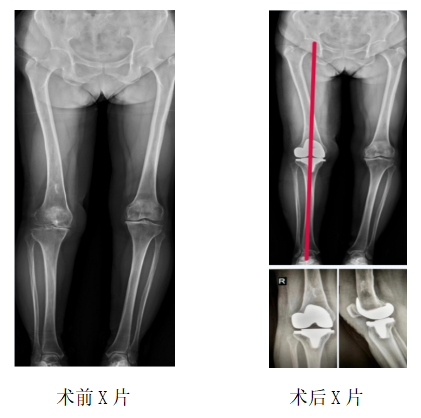

运动医疗、关节骨病科主任、主任医师丑克了解到,对平时走路散步时的疼痛程度张阿姨还能忍受,但是上下楼梯或者爬山、下蹲时就会明显感觉疼痛加重,只有休息后症状才能稍减轻,以前年轻时还有过右股骨下段化脓性骨髓炎病史,导致股骨畸形。医生经过仔细体格检查并结合影像学检查结果,诊断张阿姨患上的是“右膝关节退行性病变”。因张阿姨既往有过化脓性骨髓炎,为提高治疗效果,运动医疗、关节骨病科医护团队为张阿姨制定了个性化的手术治疗护理方案,术中使用IKPAS全膝关节导航定位技术,不开髓,减少手术创伤,精准定位截骨为张阿姨完成全膝关节置换手术。

术后医护团队对张阿姨全程进行ERAS理念管理,术后第二天她就能下床行走了,并且伤口愈合良好,也不感觉痛,术后第3天膝关节活动度可以达到90°。一周后,张阿姨出院了,她拉着丑主任手送上了锦旗:“我终于不用再受膝关节痛的折磨了,真的非常感谢您们!”

“IKPAS全膝关节手术定位系统利用传感器技术,不依赖术前患者的影像数据,通过陀螺仪及加速度计配合特定的算法,在术中实时测量股骨远端与胫骨平台的截骨角度,计算获得个性化的角度数据,以辅助医生更加精准地完成膝关节置换手术中下肢力线测量和截骨定位,被称之为智慧型膝关节置换手术。”丑克主任介绍,该定位系统可用于初次和复杂膝关节置换手术,与传统的关节置换手术相比,智慧型膝关节置换术将误差控制在1°以内,具有不需打开髓腔、减少术中术后出血、提高截骨精准度、缩短手术时间、有效降低并发症发生等优势,而且在不改变医生手术习惯和操作流程的基础上,达到了轻、快、准的微创治疗要求。

丑克主任表示,因患者有过化脓性骨髓炎导致股骨侧畸形,不适合常规的开髓定位,使用IKPAS全膝关节手术定位系统可实现不开髓手术,且有效减少术中术后出血,实现手术微创化、精细化,避免骨髓炎的再次发生。智能化手术的实施不但提升了关节骨科医疗技术水平和手术疗效,也为骨关节病患者实现更标准、更规范、更安全的治疗提供了多种选择。